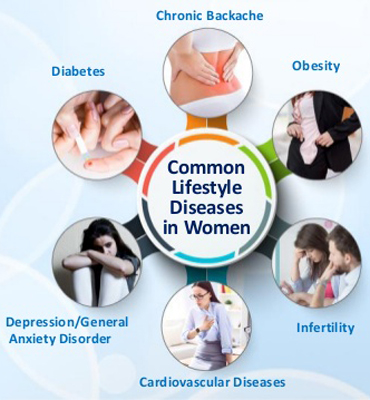

Lifestyle Disorders

- Diabetes

- Blood Pressure

- High Cholesterol

- Cancer

- Hypothyroidism

- Hyper Thyroidism

- Obesity

- Allergies

- Fevers Like Typhoid, Malaria, Chikengunya, Dengue, etc